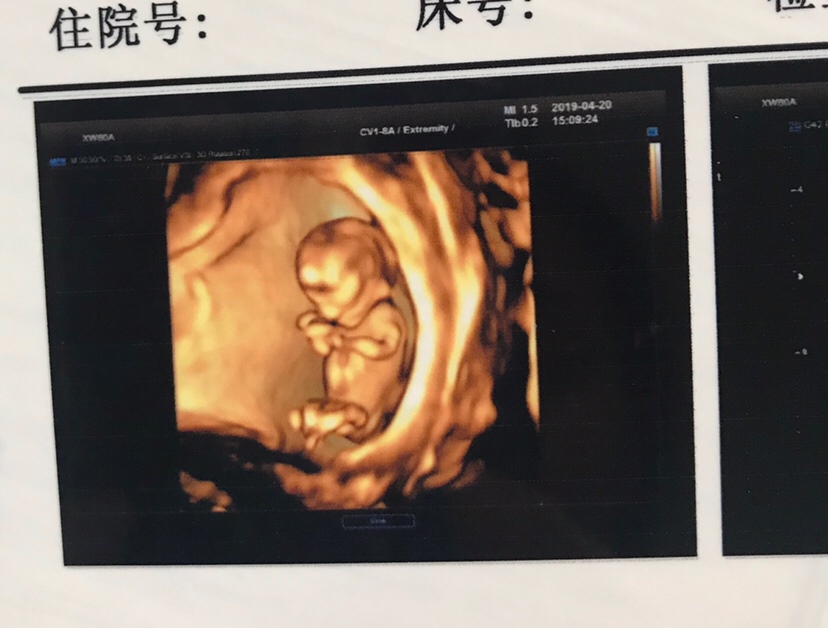

孕14周+4天

这是NT吗?

第一次见这么清晰的彩超诶

streetsfinest 💕[帖主]:对啊,我也是第一次见的。